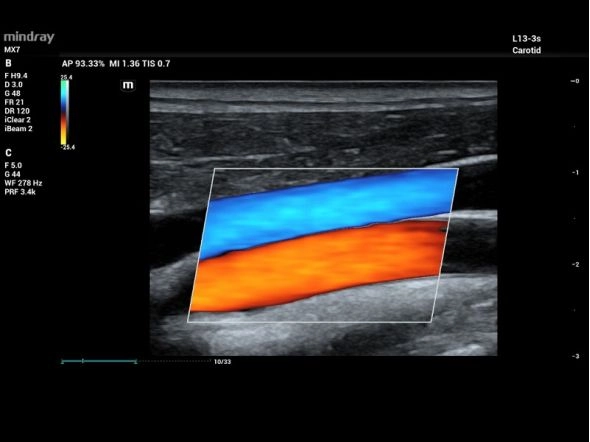

- Области применения: Абдоминальные исследования, Акушерство и гинекология, Кардиология, Сосудистые исследования, Неврология, Травматология и ортопедия, Урология, Эндокринология, Педиатрия, Неонатология, Транскраниальные исследования, Онкология

- Режимы: В-режим, М-режим, Цветное допплеровское картирование, Энергетический допплер, Импульсно-волновой допплер, цветной М-режим

- Виды допплеров: ЦДК цветовой, CWD постоянно-волновой допплер, Энергетический допплер, Импульсно-волновой допплер, Тканевой допплер

RIMT

- IMT на основе радиочастотных данных и точного измерения IMT в реальном времени

- Ранняя диагностика сердечно-сосудистых заболеваний

- Измеряет радиочастотные данные за 6 сердечных циклов и затем вычисляет максимальное значение для каждого сердечного цикла и среднее значение из 6 максимальных значений

- Высокая точность и автоматическое измерение в реальном времени могут улучшить раннюю диагностику сердечно-сосудистых заболеваний и эффективность последующего лечения

R-VQS

- Количественный анализ жесткости сосудов основан на радиочастотных данных и обеспечивает чрезвычайно точные расчеты растяжения сосудистой стенки

- Решение для ранней диагностики сердечно-сосудистых заболеваний

- После сбора данных нажмите «Полученные результаты», при этом создается отчет о PWV и коэффициенте твердости

- Высокая точность, измерение в реальном времени и автоматическое измерение обеспечивают универсальное решение для ранней диагностики сердечно-сосудистых заболеваний

Сонная артерия и яремная вена